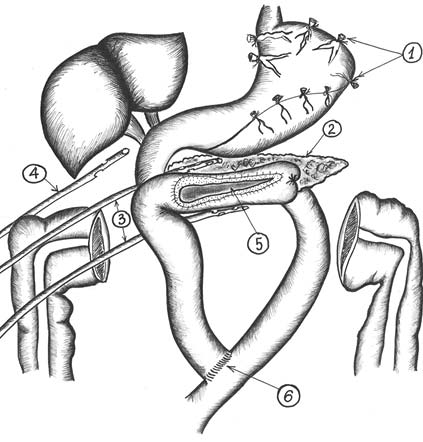

05.04.2018 пациенту были выполнены проксимальная резекция головки поджелудочной железы по C. Fray, наложение продольного панкреатоеюноанастомоза, азигопортальная дисконнекция по типу M. Hassab под сочетанной (общей комбинированной эндотрахельной многокомпонентной и эпидуральной) анестезией (рис. 3). Выполнена верхнесрединная лапаротомия с иссечением старого послеоперационного рубца. В брюшной полости выраженный спаечный процесс, преимущественно в верхнем этаже, кавернозная трансформация вен желудка, печёночно-дуоденальной и желудочно-ободочной связок. Из сращений выделены правая доля печени и передняя поверхность поджелудочной железы до крючковидного отростка. В теле железы по передней стенке визуализирован точечный дефект, сообщающийся с главным панкреатическим протоком. После пункции и вскрытия главного панкреатического протока V-образно иссечена паренхима передней стенки железы со свищевым ходом до головки, выполнена резекция головки по технике «cored out». Сформированы панкреатоеюноанастомоз и терминолатеральный анастомоз. Выполнена азигопортальная дисконнекция по M. Hassab.

Рис. 3. Схема операции: 1 — варикозно расширенные вены желудка; 2 — поджелудочная железа; 3 — дренажи к панкреатоеюноанастомозу; 4 — дренаж в подпечёночное пространство; 5 — панкреатоеюноанастомоз; 6 — межкишечный анастомоз (Roux-en-Y)